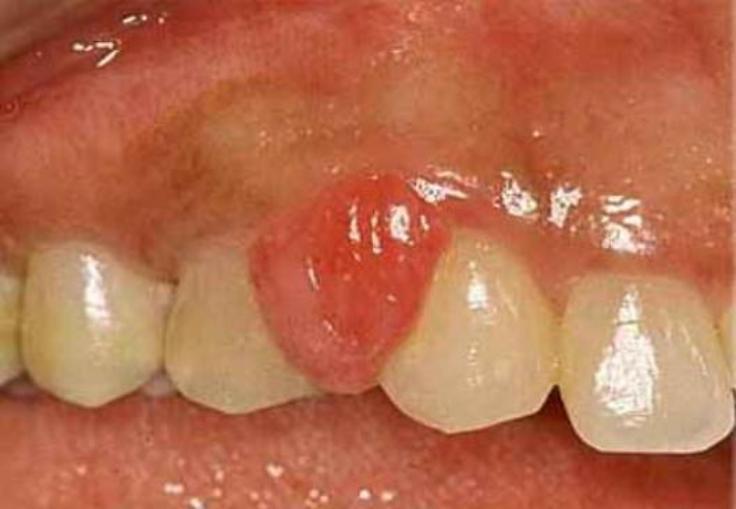

2. Piel

1. Hiperpigmentación

1. Cambios vasculares

1. Flujo sanguíneo